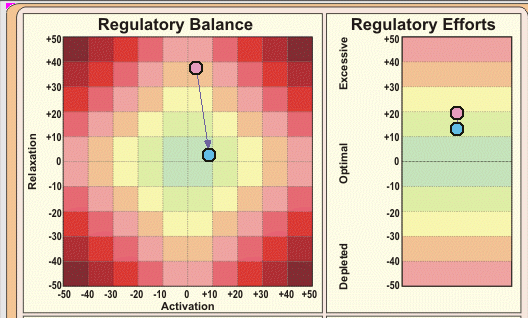

自律神経バランスを測定した結果

Hさんの自律神経バランスを測定したところ、副交感神経の働きが低下し、 自律神経全体がアンバランスな状態でした。 副交感神経がうまく働かないと、身体は常に緊張状態になります。 結果として「回復力が落ち」「痛みを感じやすい脳の状態」になってしまうのです。 つまり、トレイルランニングそのものが原因ではなく、ストレスによって痛みに敏感になっていたのです。

上記の測定結果は、現在は、TAS9VIEWという新しい自律神経バランス測定器での計測になっています